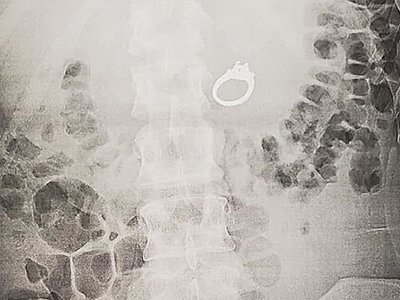

Mơ nuốt nhẫn kim cương hoá ra nuốt thật